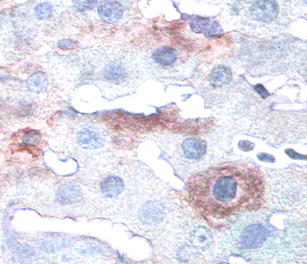

Protein levels of insulin in liver lentivirally transduced with furin-cleavable insulin. About 20% of all hepatocytes showed moderate to dense insulin immunostaining in the cytoplasm, whereas the empty vector transduced hepatocytes as well as endothelial cells and tissue macrophages (such as Kupffer cells) in the sinusoids showed no immunostaining for any islet hormone. The transduced hepatocytes showed no changes from the non-transduced cells with regard to size, glycogen content, ratio between nucleus and cytoplasm, and replication. Paraffin sections of liver were immunostained for insulin with a diaminobenzidine polymer as chromogen. Light microscopy 620×